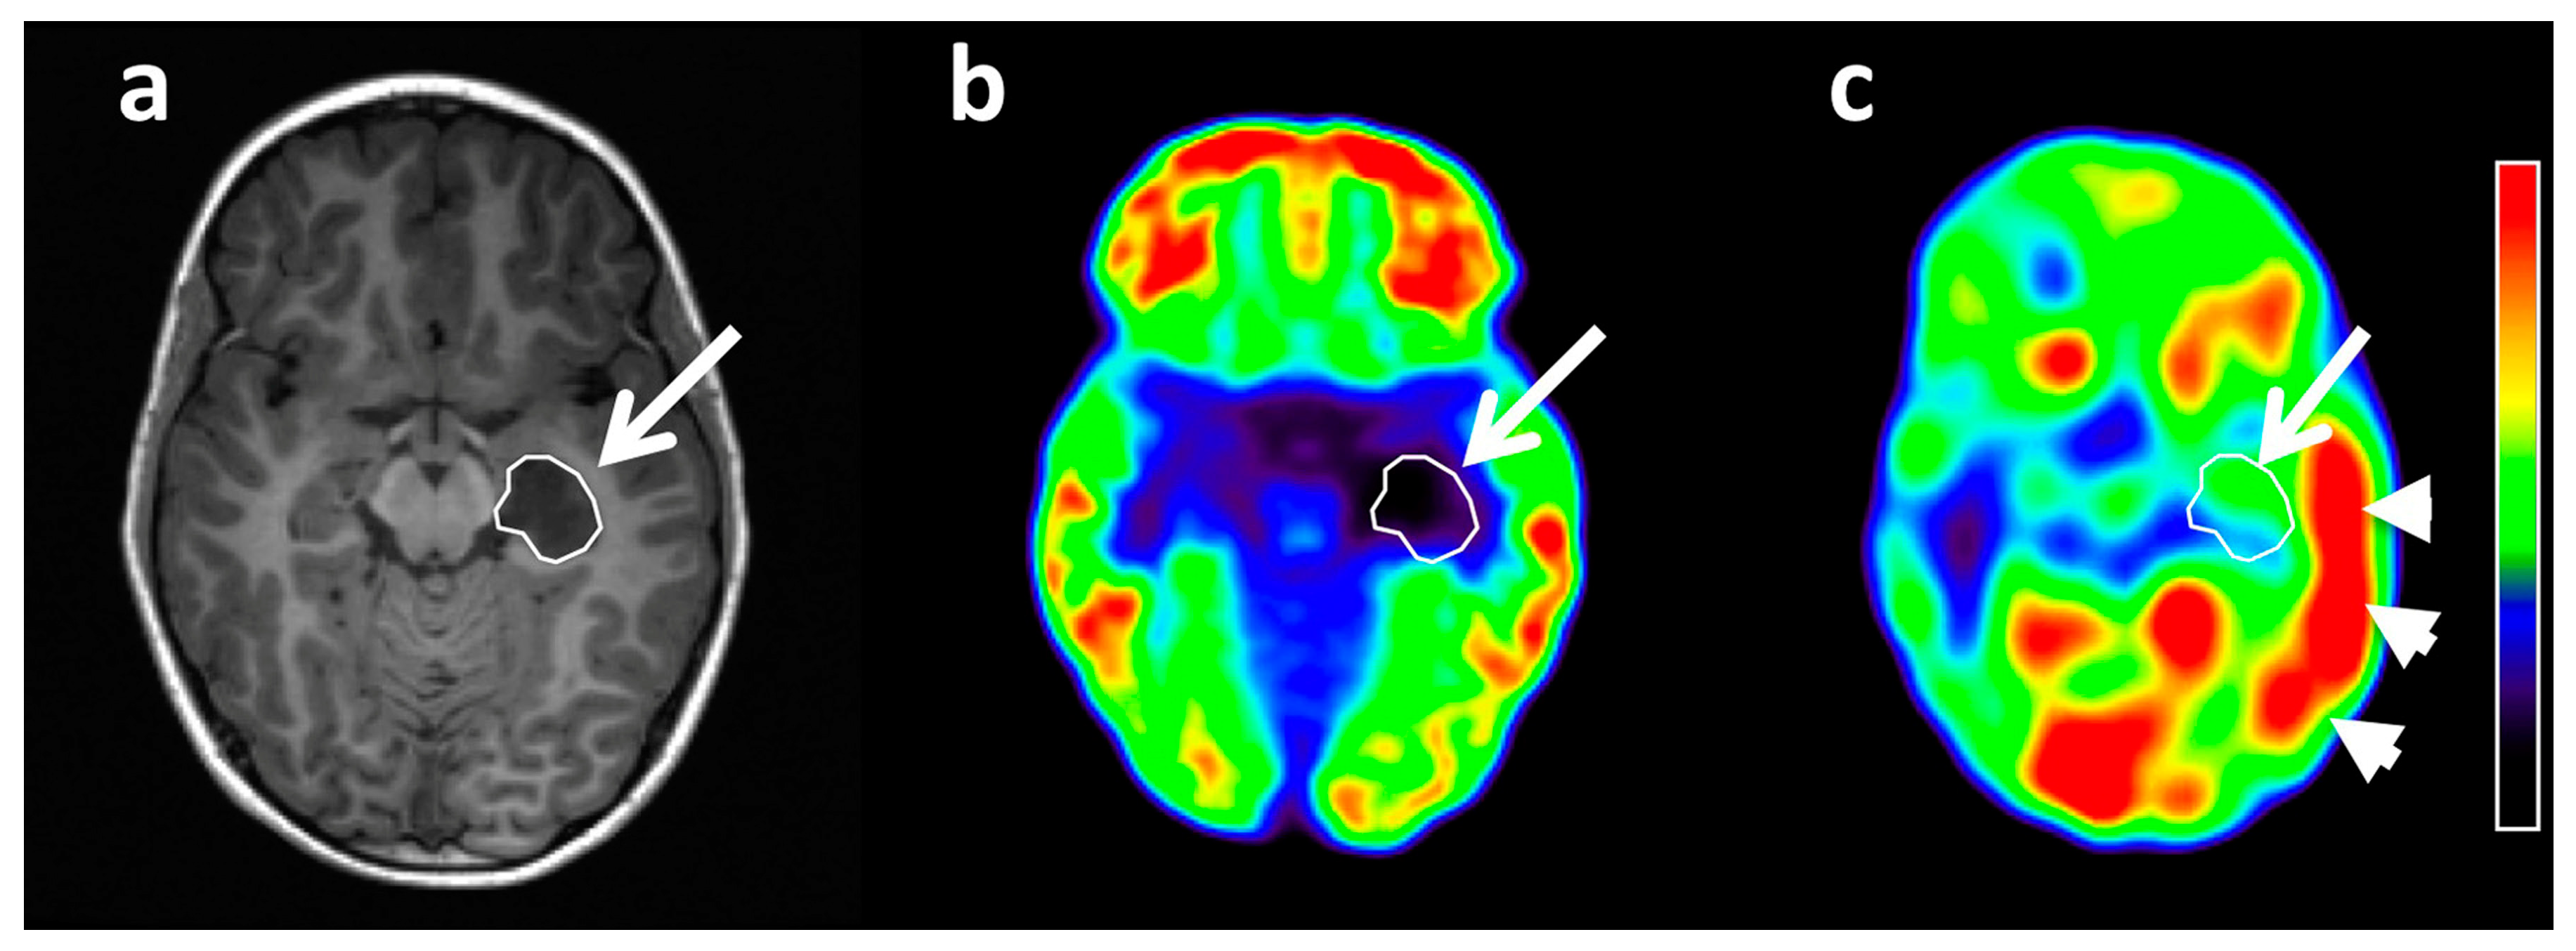

- Hutterer, M.; Ebner, Y.; Riemenschneider, M.J.; Willuweit, A.; McCoy, M.; Egger, B.; Schröder, M.; Wendl, C.; Hellwig, D.; Grosse, J.; et al. Epileptic activity increases cerebral amino acid transport assessed by 18F-fluoroethyl-l-tyrosine amino acid PET: A potential brain tumor mimic. J. Nucl. Med. 2017, 58, 129–137. [Google Scholar] [CrossRef]